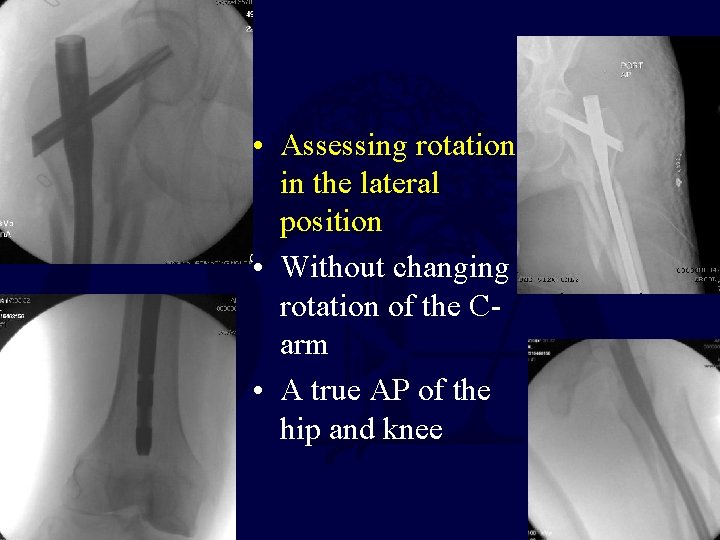

• Assessing rotation in the lateral position • Without changing rotation of the Carm • A true AP of the hip and knee